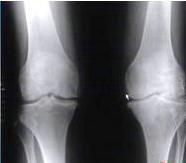

(图:钟老师初来我院膝关节红肿明显)

(图:来院复查时膝关节基本恢复正常)